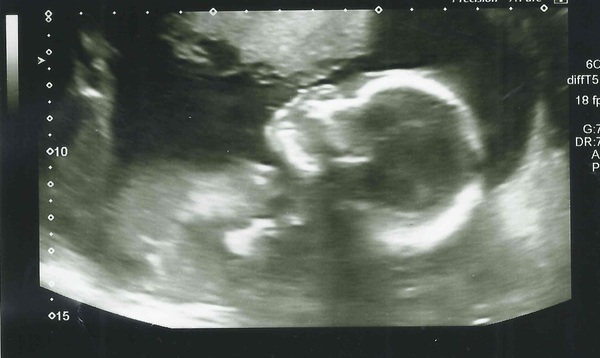

I am having a perfectly healthy and incredibly active baby girl! She spent most of the time practically latched onto the placenta while wiggling constantly, but luckily they were able to do all the measurements they needed. DD was practically the only person who guessed girl, and is very happy

MrsR what a gorgeous scan pic! And congrats!!! A week today and I'll know too! So happy for you.

Scrumptious pic MrsR!